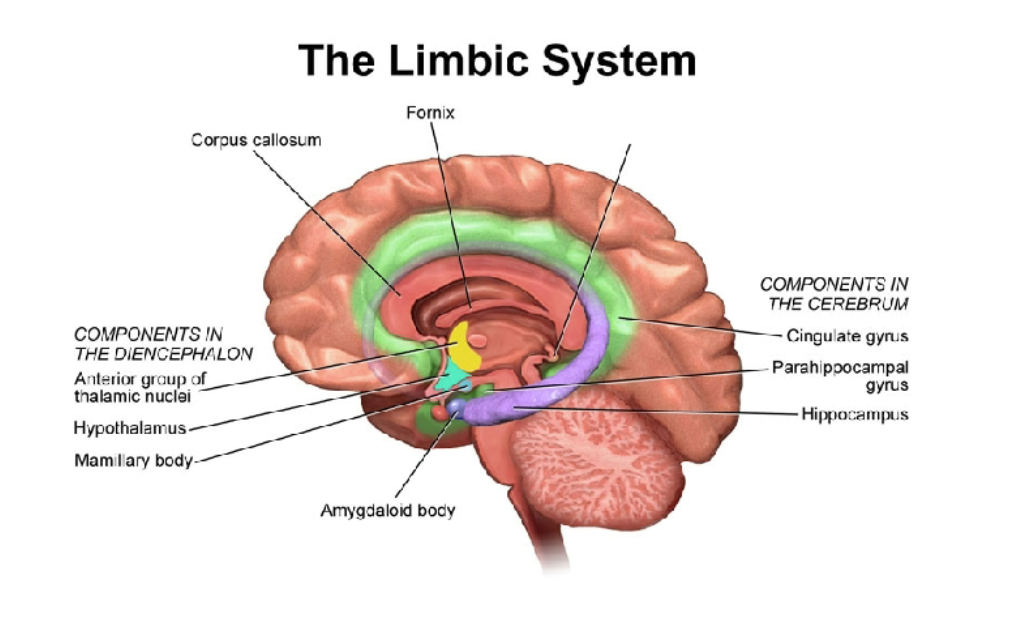

The limbic system (flowchart)

Limbic system, alternative visualization

Parts of the Limbic System